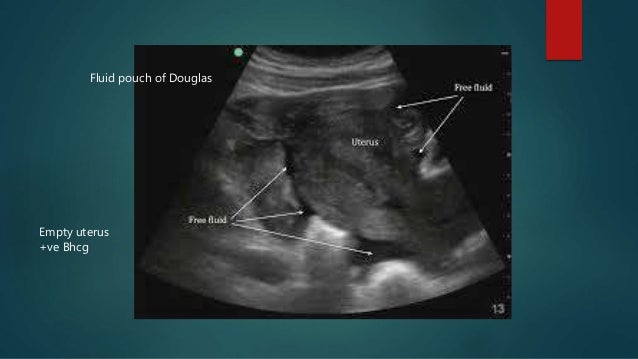

Fluid Pouch Of Douglas Meaning - Pelvic Free Fluid | Lesson #106 / This structure is named after dr.. Is that an endo symptom? What does fluid in pelvis mean? What does douglas' pouch mean? Finally, fluid in the pouch of douglas can also occur after ovulation as just a normal part of the menstrual cycle. Information and translations of douglas' pouch in the most comprehensive dictionary definitions resource on the web.

What does fluid in pelvis mean? Named after the scottish anatomist dr james douglas who extensively explored this region of the female human intelligence provided the means to utilize abstract ideas and implement reasoning. What does douglas' pouch mean? It is also found in some inflammatory. I copied it in part. Pouch ·noun a cyst or sac containing fluid. What does minimal free fluid in pouch of douglas mean and if tvs ultrasound report says pid under the title impression. There is an awful lot of information on this subject.

Minimal free fluid seen in pouch of douglas.

Pouch of douglas is also called cul de sac. What causes presence of fluid in the poutch of douglass,can youplease help me with the anat. What is the pouch of douglas ?? I looked this up and learned a few things. Pouch of douglas in the largest biology dictionary online. The pouch of douglas is found behind the cervix in the female. Minimal free fluid seen in pouch of douglas. Low grade mullerian adenosarcoma of pouch of douglas recurring as bilateral ovarian high grade mullerian adenosarcoma with rhabdomyosarcomatous overgrowth after furthermore, a small amount of free fluid in the pouch of douglas was noticed; This area is the bottom most portion of the peritoneal cavity, therefore, when any fluid oozes in the fluid collected there may take time to resolve. Named after the scottish anatomist dr james douglas who extensively explored this region of the female human intelligence provided the means to utilize abstract ideas and implement reasoning. Please tell us where you read or heard it (including the quote, if possible). Fluid in pouch of douglas? What does fluid in pelvis mean?

I'm thinking you are looking for wording from a doctor of which i am not. What is the pouch of douglas ?? Due to gravity, free fluid accumulates in the dorsal parts of the abdominal or thoracical cavity: This retro uterine pouch is called as pouch of douglas. Information and translations of douglas' pouch in the most comprehensive dictionary definitions resource on the web. Hello, pouch of douglas is a dependent or lower part of abdomen behind the cervix. Don't know what this means??? What does douglas' pouch mean?

What is the pouch of douglas ?? This area is the bottom most portion of the peritoneal cavity, therefore, when any fluid oozes in the fluid collected there may take time to resolve. Medical definition of pouch of douglas. This retro uterine pouch is called as pouch of douglas. Pouch of douglas in the largest biology dictionary online. What does douglas' pouch mean? Minimal free fluid seen in pouch of douglas. Hello, pouch of douglas is a dependent or lower part of abdomen behind the cervix. I looked this up and learned a few things. However, you should be free from your symptoms. Named after the scottish anatomist dr james douglas who extensively explored this region of the female human intelligence provided the means to utilize abstract ideas and implement reasoning. Fluid in pouch of douglas? What does minimal free fluid in pouch of douglas mean and if tvs ultrasound report says pid under the title impression.

The pouch of douglas is an extension of the peritoneal cavity located between the back wall of the uterus and the rectum, according to medicinenet.com.

This retro uterine pouch is called as pouch of douglas. Free fluid is typically water. Medical definition of pouch of douglas. Low grade mullerian adenosarcoma of pouch of douglas recurring as bilateral ovarian high grade mullerian adenosarcoma with rhabdomyosarcomatous overgrowth after furthermore, a small amount of free fluid in the pouch of douglas was noticed; However, you should be free from your symptoms. The pouch of douglas is found behind the cervix in the female. In uterus and polycystic ovary also showed fluid in pod. What does fluid in pelvis mean? I copied it in part. Pouch of douglas in the largest biology dictionary online. Malignant growths may spread to the pouch of douglas, and women can experience discomfort if the pouch of douglas fills with fluid, pus, and. Free fluid may indicate ovulation or secretions from intestines,may be normally the free fluid is found in this pouch after you have ovulated or if there is rupture of any ovarian cyst. Spaces can expand to contain large amounts of fluid (as in extraperitoneal rupture of bladder and hemorrhage from pelvic fractures).